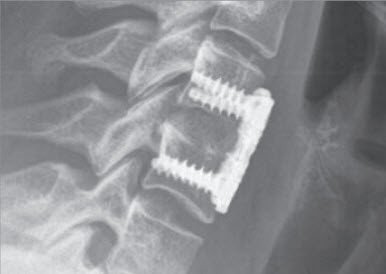

Um Form und Stabilität der Halswirbelsäule zu erhalten, wird die Bandscheibe oder der Wirbelkörper ersetzt, und zwar mit geeigneten künstlichen Implantaten, Beckenknochen oder Knochenersatz. Sie haben die Funktion eines Platzhalters anstelle der entfernten Bandscheibe oder des Wirbelkörpers. Eine Plattenfixation kann erforderlich sein, wenn es darum geht, die Stabilität der Halswirbelsäule zusätzlich zu verbessern.

Als neuere Methode kann in gewissen Fällen die Bandscheibe mit einer beweglichen Prothese ersetzt werden. Damit wird eine Versteifung vermieden, und die potenzielle Überbelastung der angrenzenden Bandscheiben und Gelenke entfällt.